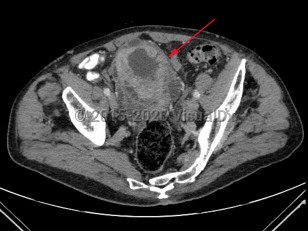

Bladder cancerBladder cancer